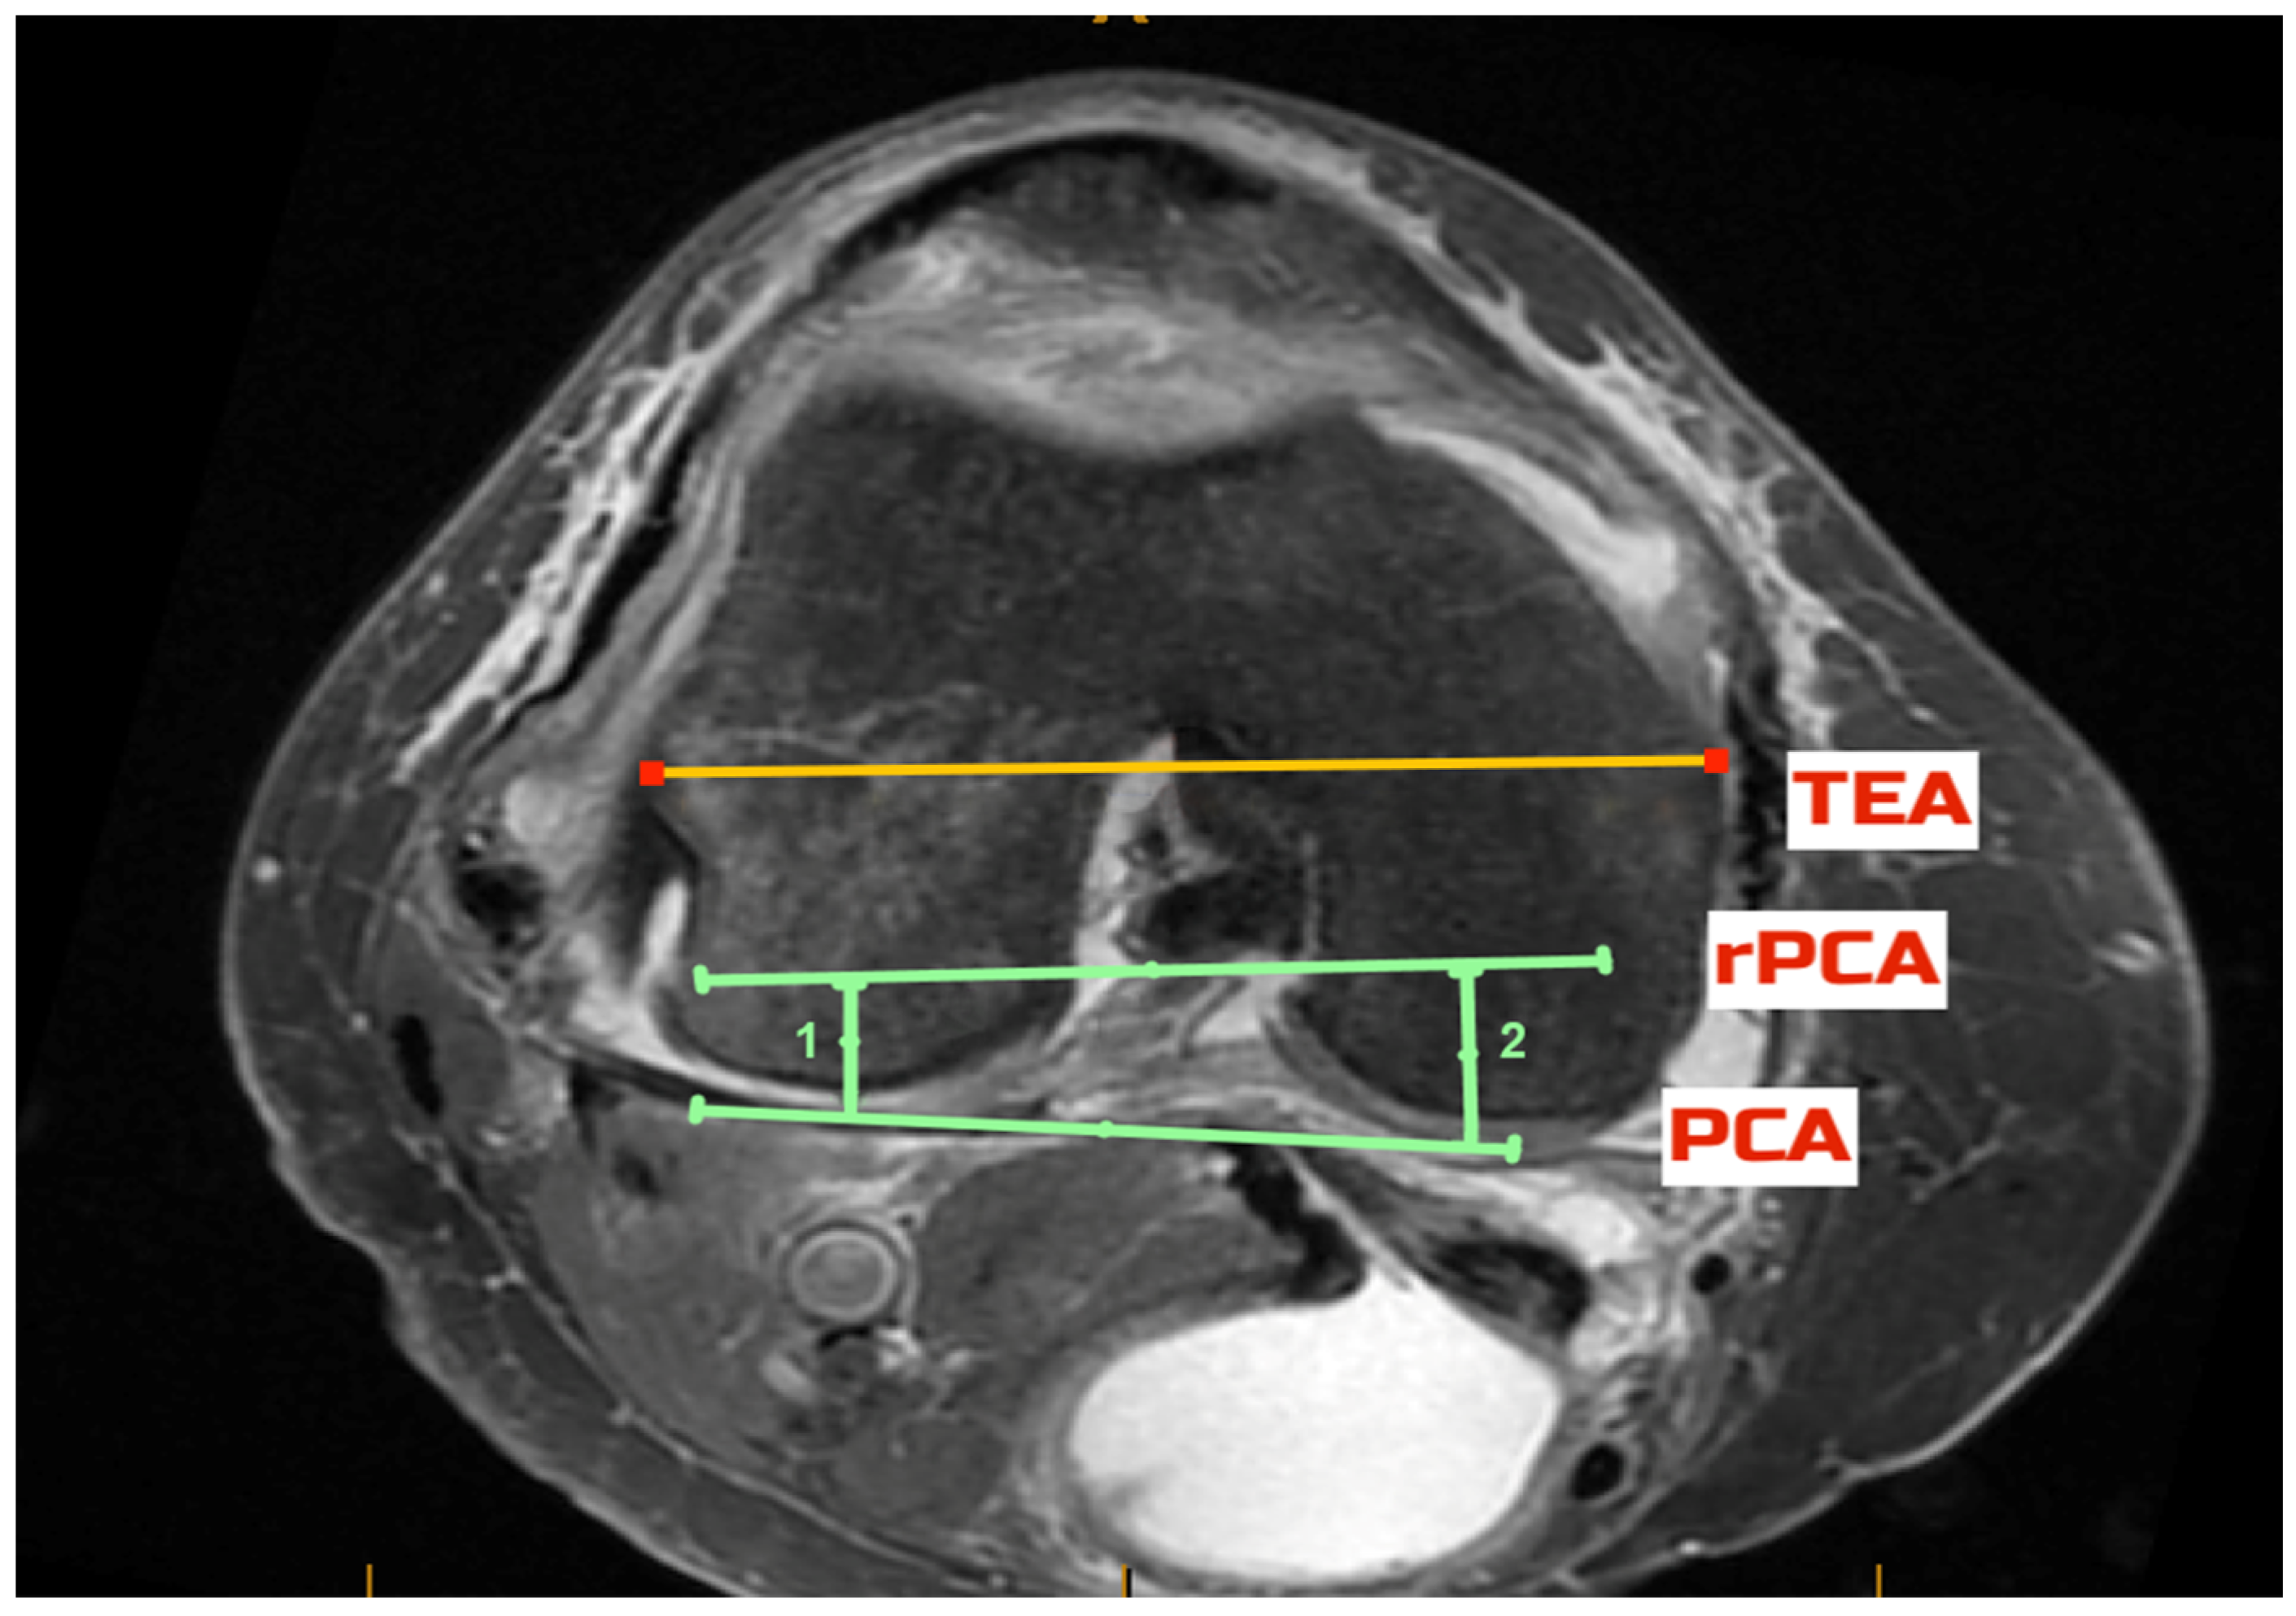

2.5. Radiological Outcomes